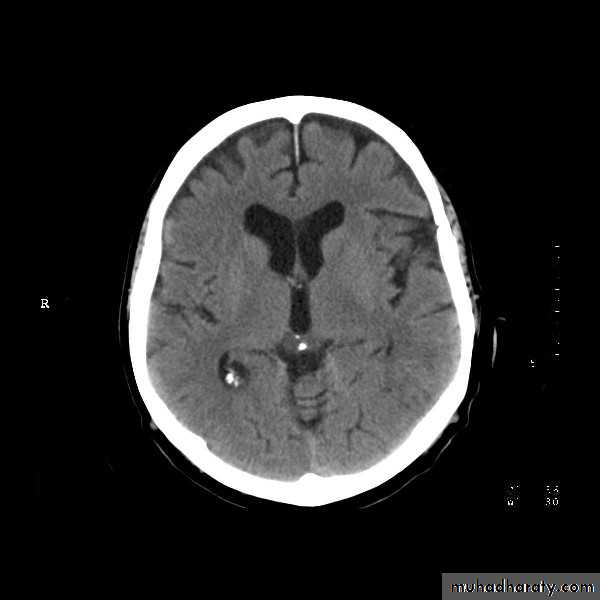

Normal Brain

34

Normal Ventricles